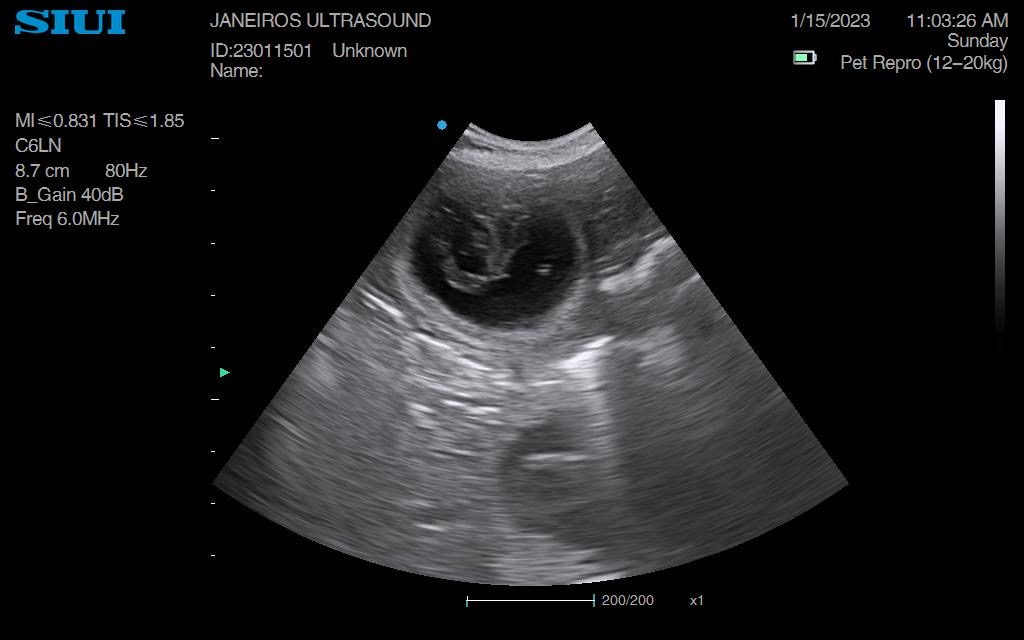

Nala came in for a scan just under 2wks ago. The sacs were tiny so we knew she had only just taken – much later than owner originally thought.

All I could do was confirm pregnancy at this stage and book her in for a rescan. We saw 3 sacks.

Spring forward to today. Measurements taken suggested 5wks and 1 day gestation and 6 sacs!!

Confirmed heartbeats on each puppy. All cooking away nicely.